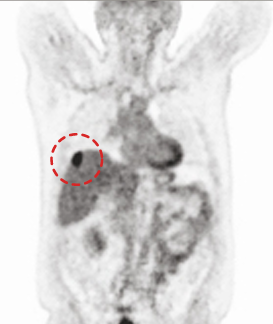

CASE #2 [liver cancer]

15 min (50%) Scan Without Denoising

15 min (50%) Scan With Denoising

30 min (100%) Scan Standard